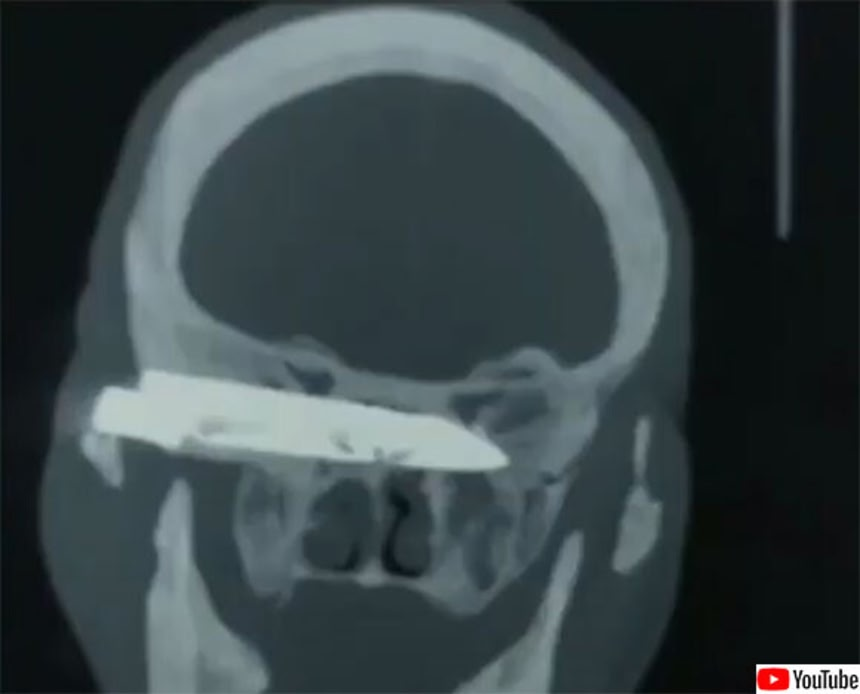

診察の結果、頭蓋骨の底を支えている靭帯が大きく損傷し、背骨の一番上から切り離されていることが判明した。

医師による診断は「bilateral atlanto occipital joint dislocation」で、彼の頭は「首の付け根からほぼ完全に切断」された深刻な状態だったという。

手術は、数時間がかりで損傷した部分をプレートと固定具でつなぐという大手術だった。

切断というより、頚椎と頭蓋骨の間の関節が完全に脱臼した状態だね。

靭帯も切れて首がプランプランな状態。

頭蓋骨と頚椎をつなぐ関節が完全に離れてしまうような脱臼で、しかも記事では骨以外の靭帯とかも全部おシャカって。